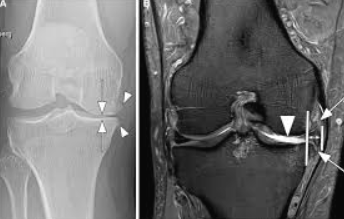

영상 검사

엑스레이로 관절 간격, 연골 소실, 변형 등을 확인하며, 필요시 MRI로 연골 및 인대 상태를 정밀하게 평가합니다.